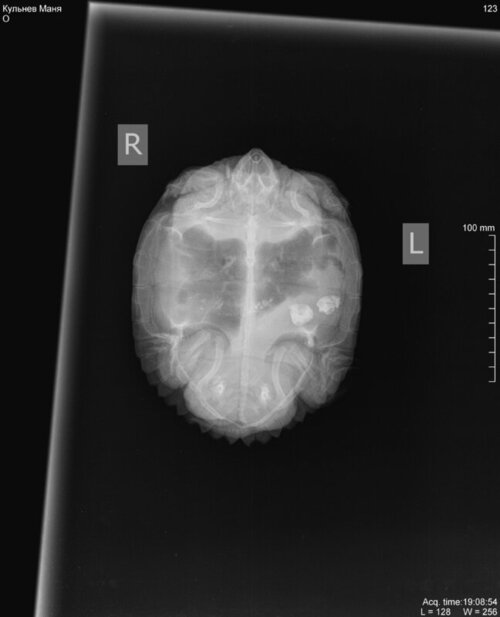

Здравствуйте.Красноухая черепаха.Самка.Точный возраст не известен,но довольнно крупная. Около 2 недель назад проглотила несколько камней.В последние несколько дней у черепахи пропал стул.Аппетит нормальный. Так же часто пускает пузыри воздуха изо рта.Мало плавает.Большую часть времени проводит с высунутой головой из воды.В клинике ,где делали сники ,сказали,что либо камни выйдут сами ,либо нужна хирургическая операция,которую в нашем городе не делают.Что можно сделать для того,что-бы камни вышли естественным путём?

Кульнев Маня_DX_20221025_190854_1.jpg